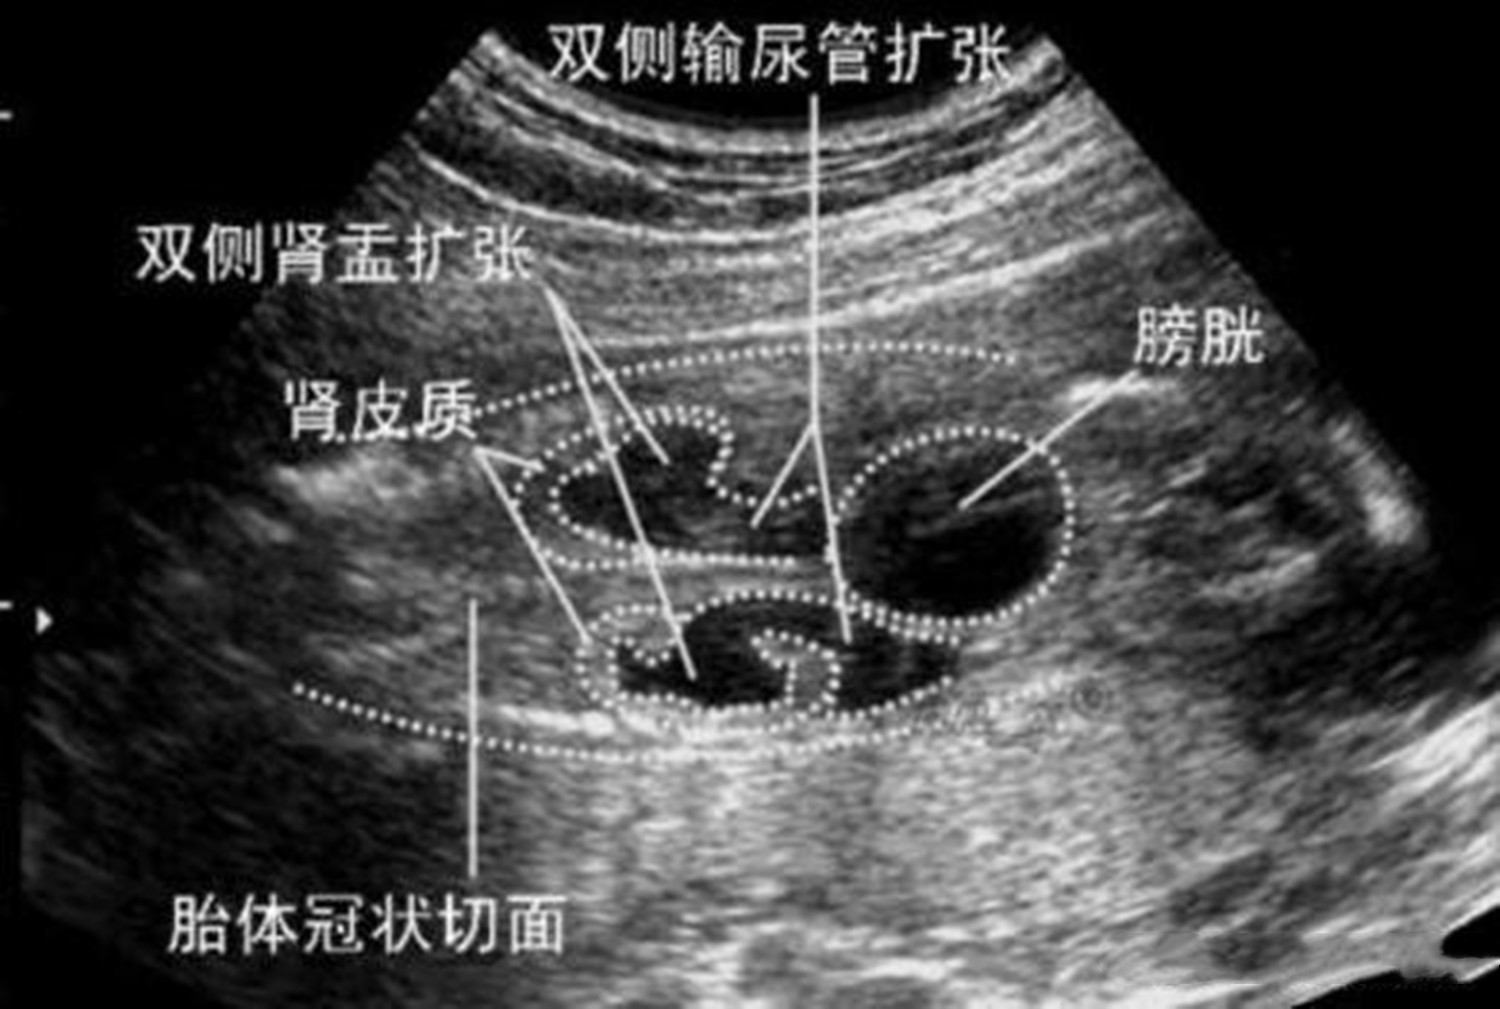

照四维彩超,除了看孩子的容貌外,还要会看孩子的外观结构,确定宝宝拥有清晰可见的五官后,还可以看出颅骨光环,甚至还可以看清小脑以及脑回路结构。

这时家长可以仔细观察一下,孩子的脑中线是不是在正中间的位置,双侧丘脑的发育情况,以及小脑延髓池是否正常发育,这些数据都是非常清晰的。

在四维彩超的报告上,会显示出宝宝的内脏发育是否完全,肠管是否正常,这些是很多孕妈妈或者是家人都没有注意到的地方。

在报告单上,可以看见胎儿的双顶径、股骨长等数据,看好这些数据,是可以看清楚孩子的生长情况的。

同时四维彩超也可以看出孩子的动脉血流情况,看看孩子的心跳是否在正常范围内。

3)了解胎儿发育环境好坏

看过报告单的孕妈妈应该记得,在报告单上会写着羊水高度、胎盘发育情况,以及宝宝是否正常,这些信息会告诉你孩子的生活环境是好是坏,自己有没有被脐带绕颈等。